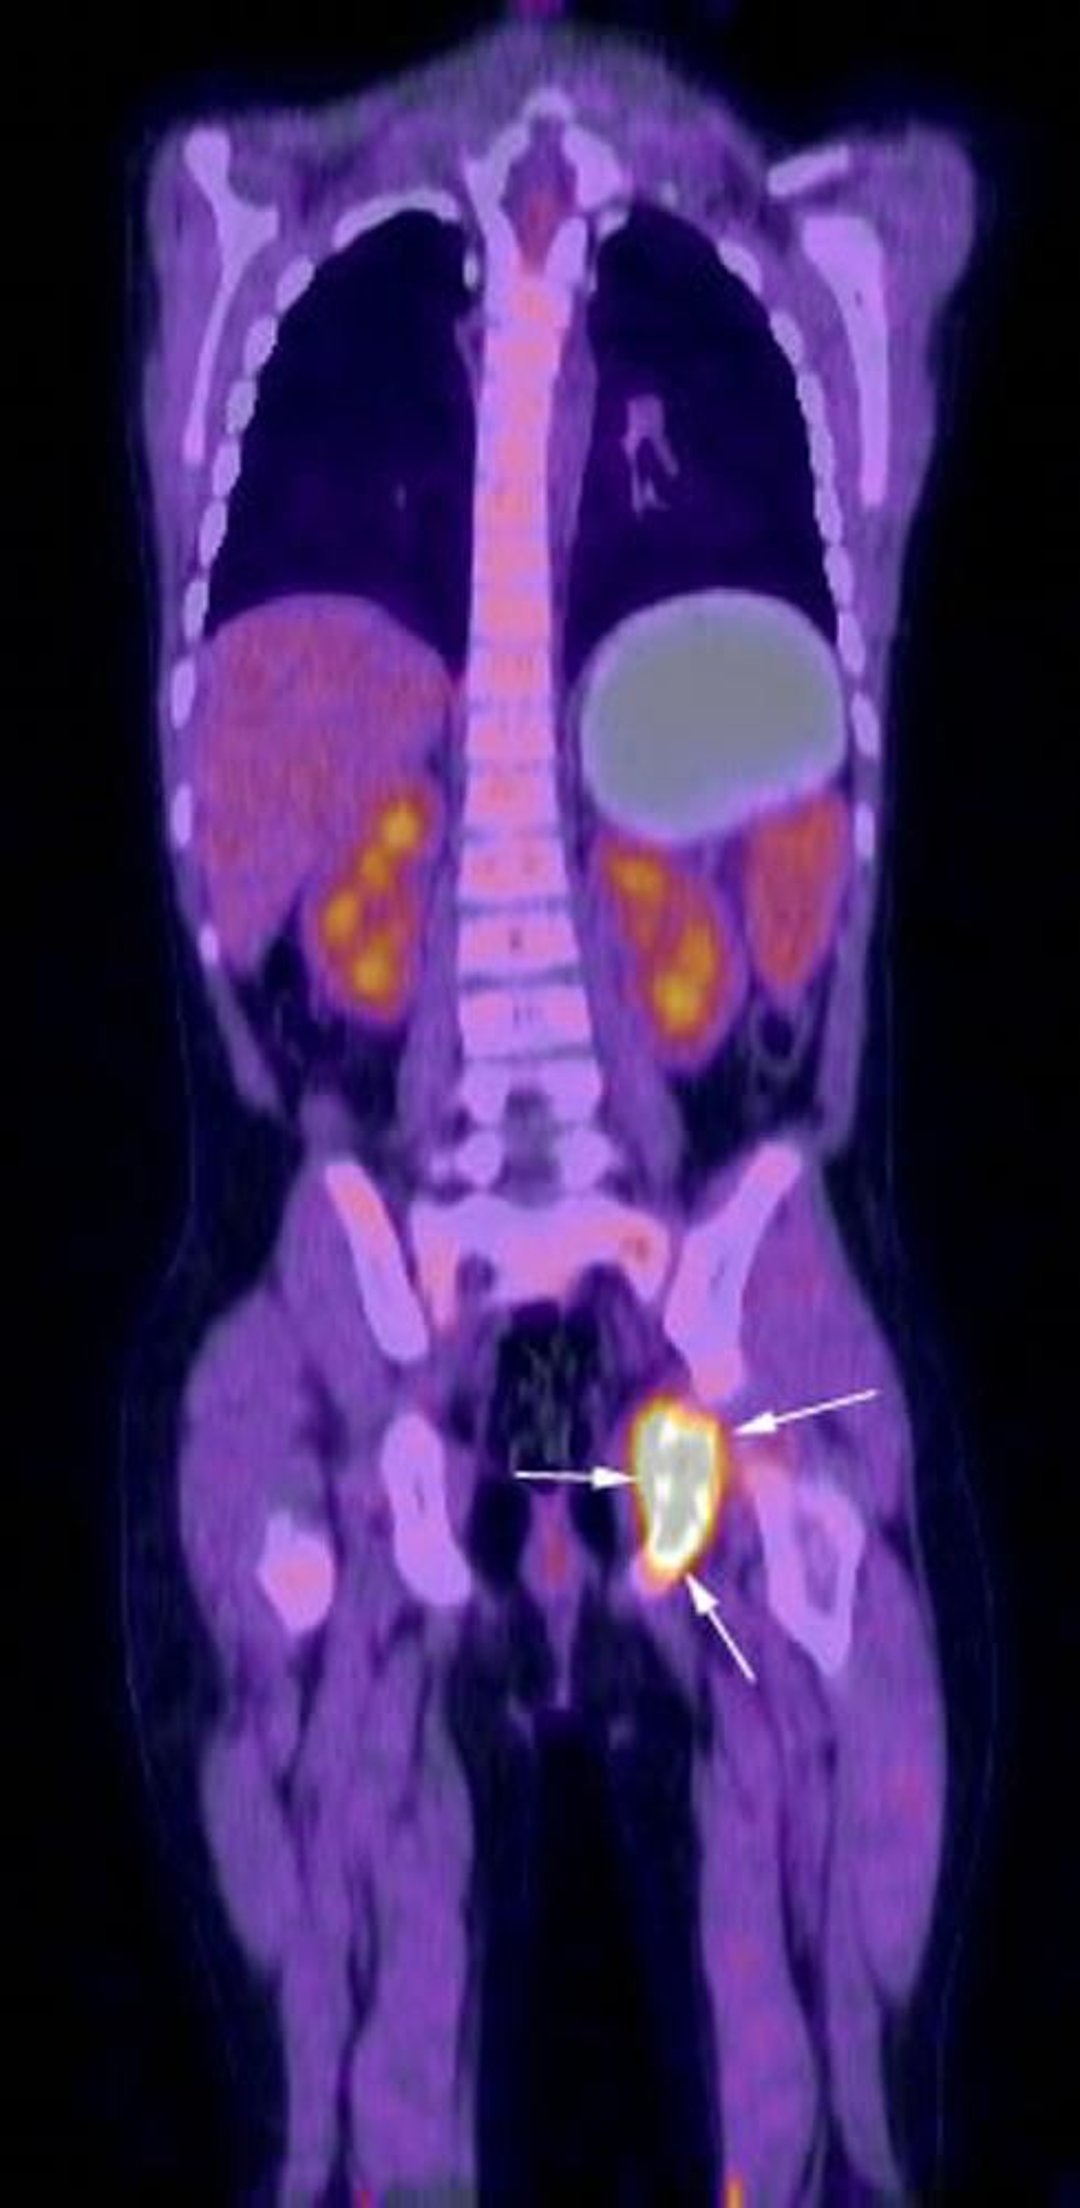

L'image de reconstruction coronale d'un examen PET-TDM FDG montre une activité métabolique intense dans la région de l'ischion gauche (flèches) correspondant à une histiocytose à cellules de Langerhans connue chez le patient.

Image courtoisie de Hakan Ilaslan, MD.